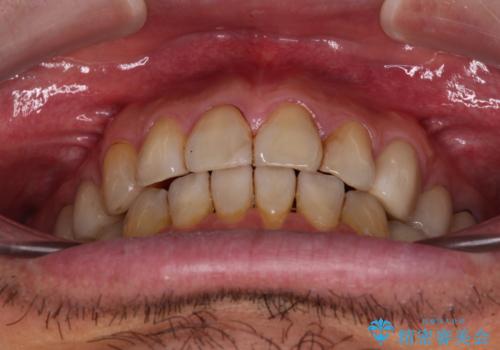

痛みは速やかに引き、銀歯や黒く変色したむし歯がセラミッククラウンで自然な色合いに仕上がり、患者様には大変満足していただきました。